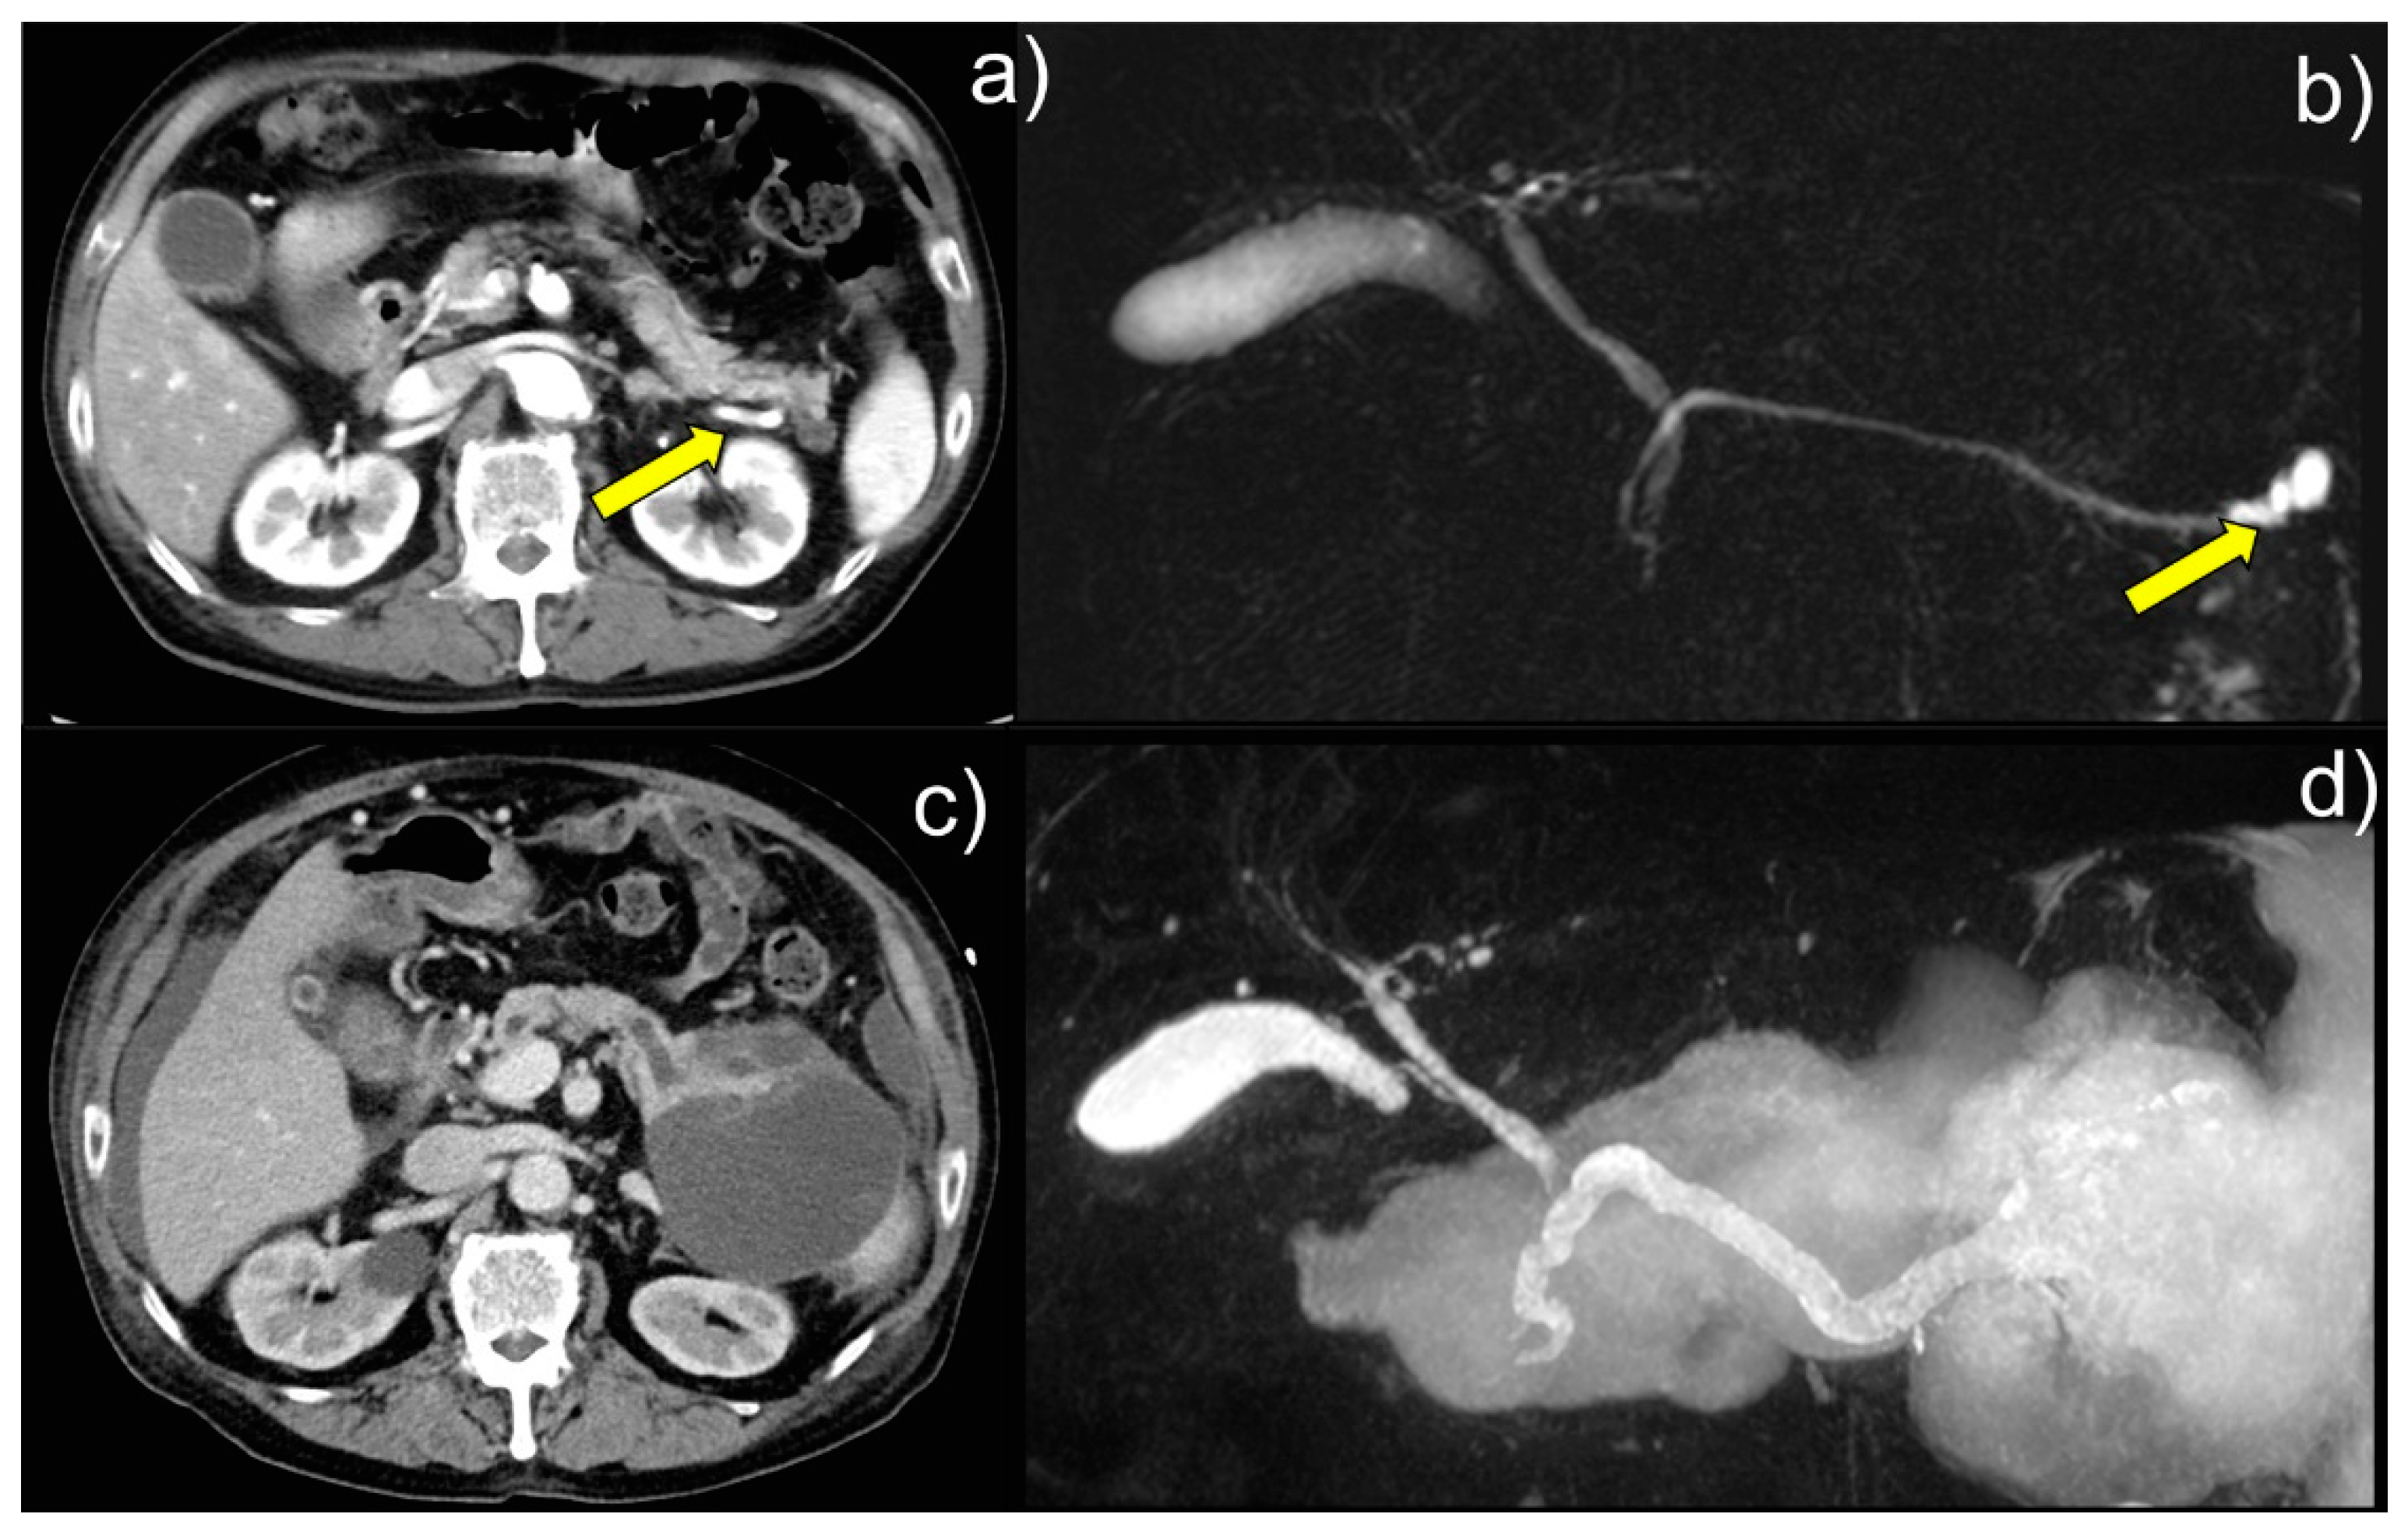

A 62-year-old Japanese man was admitted to our hospital with respiratory distress. Enhanced computed tomography (CT) and magnetic resonance cholangiopancreatography (MRCP) showed that the patient had a branch duct-type IPMN 22 mm in size. (a) At the patient’s initial presentation to hospital, CT image showed a cystic lesion in the pancreatic tail (arrow). (b) MRCP image showed a 22-mm cystic lesion in the pancreatic tail (arrow). The mass increased in size over approximately three months but was neglected. Nine years later, during hemodialysis at the Department of Nephrology, Shimada General Medical Center, for respiratory failure caused by acute renal failure, the now 71-year-old patient was found to have a pancreatic cystic mass on a CT scan and was referred to the Department of Gastroenterology for further examination and treatment. Laboratory examination showed serum levels of the tumor markers CEA of 6.4 ng/mL (standard value, ≤5.0) and CA19-9 of 56.6 U/mL (standard value, ≤37.0). MRCP showed that the main pancreatic duct of the patient was dilated to 8 mm in diameter, with a large ruptured pancreatic cyst of over 120 mm in diameter being suspected, and enhanced CT showed possible intraperitoneal penetration. (c) CT image showed suspected intraperitoneal penetration, and (d) MRCP image showed dilation of the patient’s main pancreatic duct to 8 mm in diameter. A large, ruptured pancreatic cyst (≧120 mm in diameter) was also suspected. Although no high-risk stigmata were noted, the cyst diameter increased to ≥30 mm. The contrast-enhanced cyst wall and main pancreatic duct ranging from 5 to 9 mm in diameter indicated a cause for concern [1]. Therefore, we performed endoscopic nasopancreatic drainage (ENPD) and serial pancreatic juice aspiration cytological examinations (SPACE).

Figure 1. Intraductal papillary mucinous neoplasms (IPMNs) represent approximately 1% of all pancreatic neoplasms and are cystic pancreatic lesions with mild to severe atypia. They are divided into main-duct IPMN, branch-duct IPMN, and mixed-type IPMN [1,2,3]. Understanding the characteristic cellular findings from cytological examination and referring to appropriate cytological diagnosis and histological subtypes is desirable [2,3]. Intestinal-type IPMNs comprise approximately 40 % of IPMNs [4]. Colloid carcinoma (CC) of the pancreas is a rare subtype of pancreatic cancer, only 1-3% of the malignant tumors of the exocrine pancreas [5]. Pancreatic CC may arise in an intestinal-type IPMN or mucinous cystic neoplasm [5]. Cytologically, some malignant floating cells within the mucin of the CC show signet-ring cell features [5].